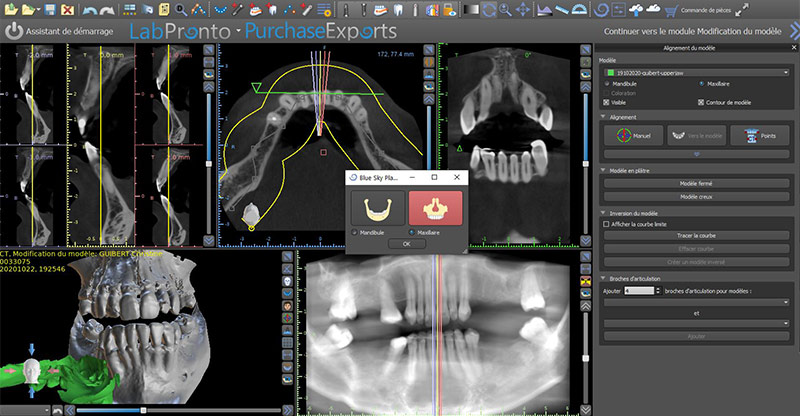

Le matching consiste à superposer les données STL aux données DICOM. Il existe plusieurs méthodes pour réaliser la superposition : point par point, dent par dent ou automatique. Avec la nouvelle version, le matching se fait automatiquement de manière très précise.

Fig. 04 : le matching.

La fusion des images 3D et 2D est alors possible et réalisée. Pour vérifier le bon matching, nous vérifions si les contours du fichier STL se superposent correctement sur les contours des dents du dicom.

Fig. 05 : contrôle du matching.

Cinq différentes fenêtres vont possiblement s’ouvrir simultanément, une coupe transversale, une coupe sagittale, une coupe axiale, la courbe panoramique et une vue 3D.

Fig. 06 : perspective, implant tangentiel 5.